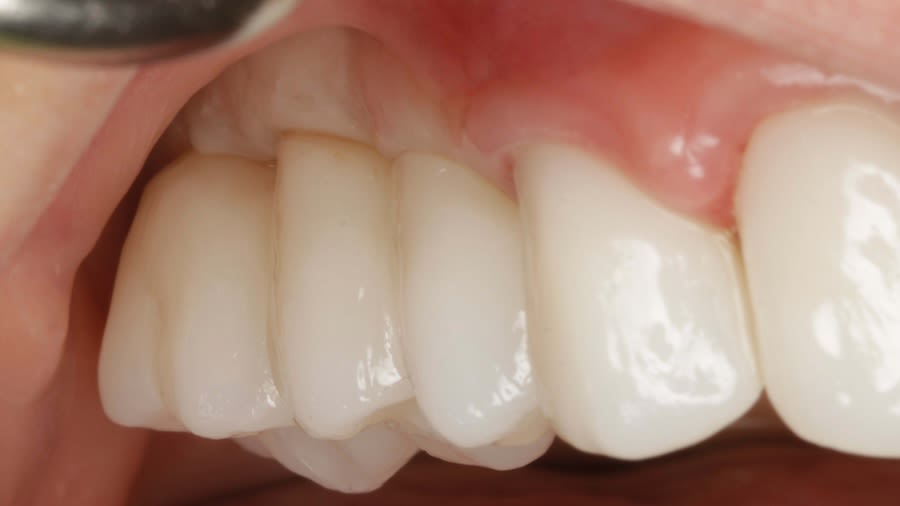

Case 1 (Figure 3 through Figure 24) depicts a 3-year follow-up of combined osseodensification sinus protocol IV in a severely resorbed maxillary ridge with ≤0.5 mm bone height in molar sites and horizontal deficiency at the first premolar site, using a two-stage approach for implant placement.

The presented protocol describes a crestal sinus elevation procedure using osseodensification burswith vertical stops (Versah) in severe cases with <2 mm of residual bone as a predictable technique, with successful bone regeneration for second-stage implant placement with subsequent stable peri-implant bone level at 3-year follow-up. This technique, thus, offers a simplified, minimally invasive, and less traumatic method for sinus floor elevation in cases with severe residual bone height loss.